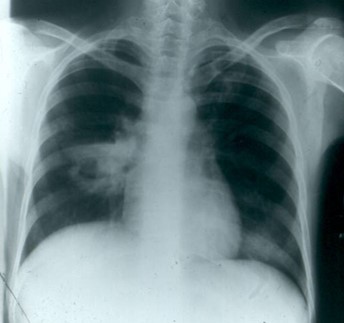

Pulmonary infection with nocardia may mimic tuberculosis in all of its forms (cavitary,

miliary, or nodular infiltrates) and/or tumor (mass lesions) as seen in the two presented

cases - the one on the left with a cavitating mass lesion, the one on the right with

an apical cavitary lesion.